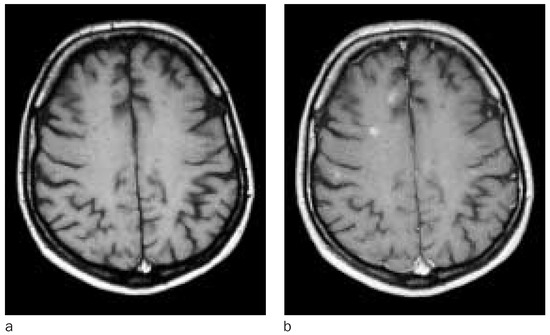

Réflexions sur la morphologie de la schizophrénie

by E. Wildi and V. Djientcheu

The pathological anatomy of schizophrenia has been studied well in autopsy series between 1935 to 1960. Morphologic data provided by MRI are different from that obtained at autopsy. The authors present a review of the literature, an analysis of the results, hypotheses and a basis for reflection.

Analysis demonstrates highly statistically significant differences with the X2 and F test with autopsy series showing that the schizophrenic patient is different from the non-schizophrenic in that the lateral ventricles are of small size, the brain is heavier, the Reichardt’s coefficient is smaller and the goniosynapses are more frequent. Senile plaques and Alzheimer’s neuronal lesions in brain atrophy related to aging are uncommon. Anoxic lesions in the brain and some arteriolar lesions are less frequent (dysphoric angiopathy and hypertensive arteriosclerosis).

The cerebral metabolism is a particular one with a high resistance to spontaneous convulsive seizures and the anoxic state of the induced seizures. Full article